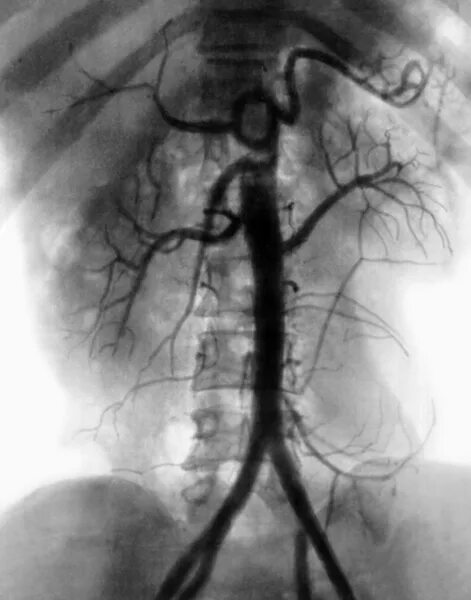

Тромбоз аневризмы аорты